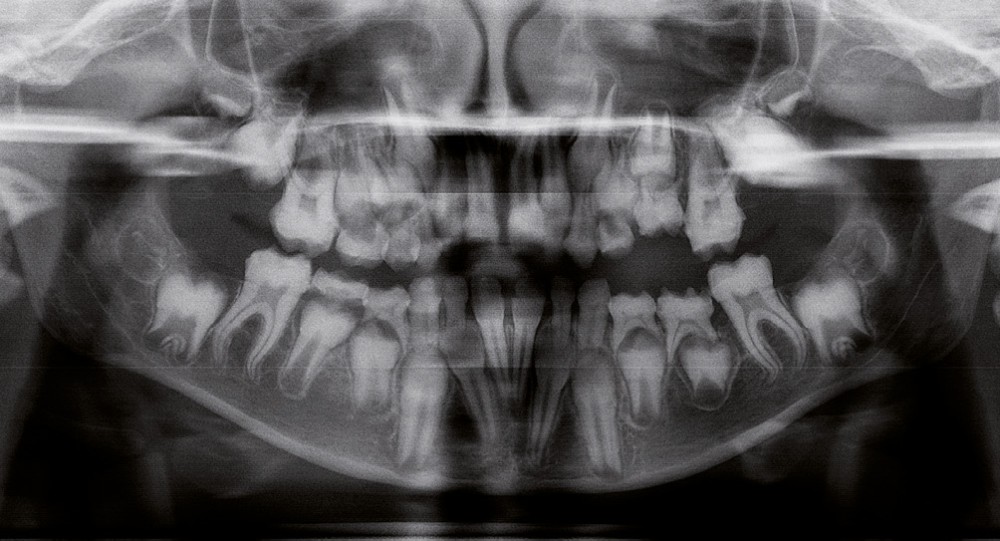

Il existe des anomalies dentaires (tabl. I) [1-12], mais aussi occlusales associées aux AI (fig. 1 et 2).

Selon de nombreuses études, l’anomalie occlusale la plus fréquemment retrouvée en association avec les AI est l’infraclusion antérieure, puisqu’elle est retrouvée chez 22 à 64 % des patients présentant cette affection, et encore plus chez les femmes [2,8,13-19]. Cette anomalie touche tous les types d’AI mais à des degrés très divers. Son incidence semble élevée dans les formes hypominéralisées, moindre dans les formes hypoplasiques et nettement moindre dans les formes hypomatures [8,17,18]. La sévérité de l’atteinte amélaire ne semble pas corrélée avec la présence ou l’intensité de cette malocclusion [17].

En 1982, Rowley et al. [18] ont montré que 44 % des patients atteints d’AI dans leur échantillon, présentaient un angle plan maxillaire (épine nasale antérieure – épine nasale postérieure) /plan mandibulaire (point gonion – point menton) supérieur à 34°, alors que la norme…